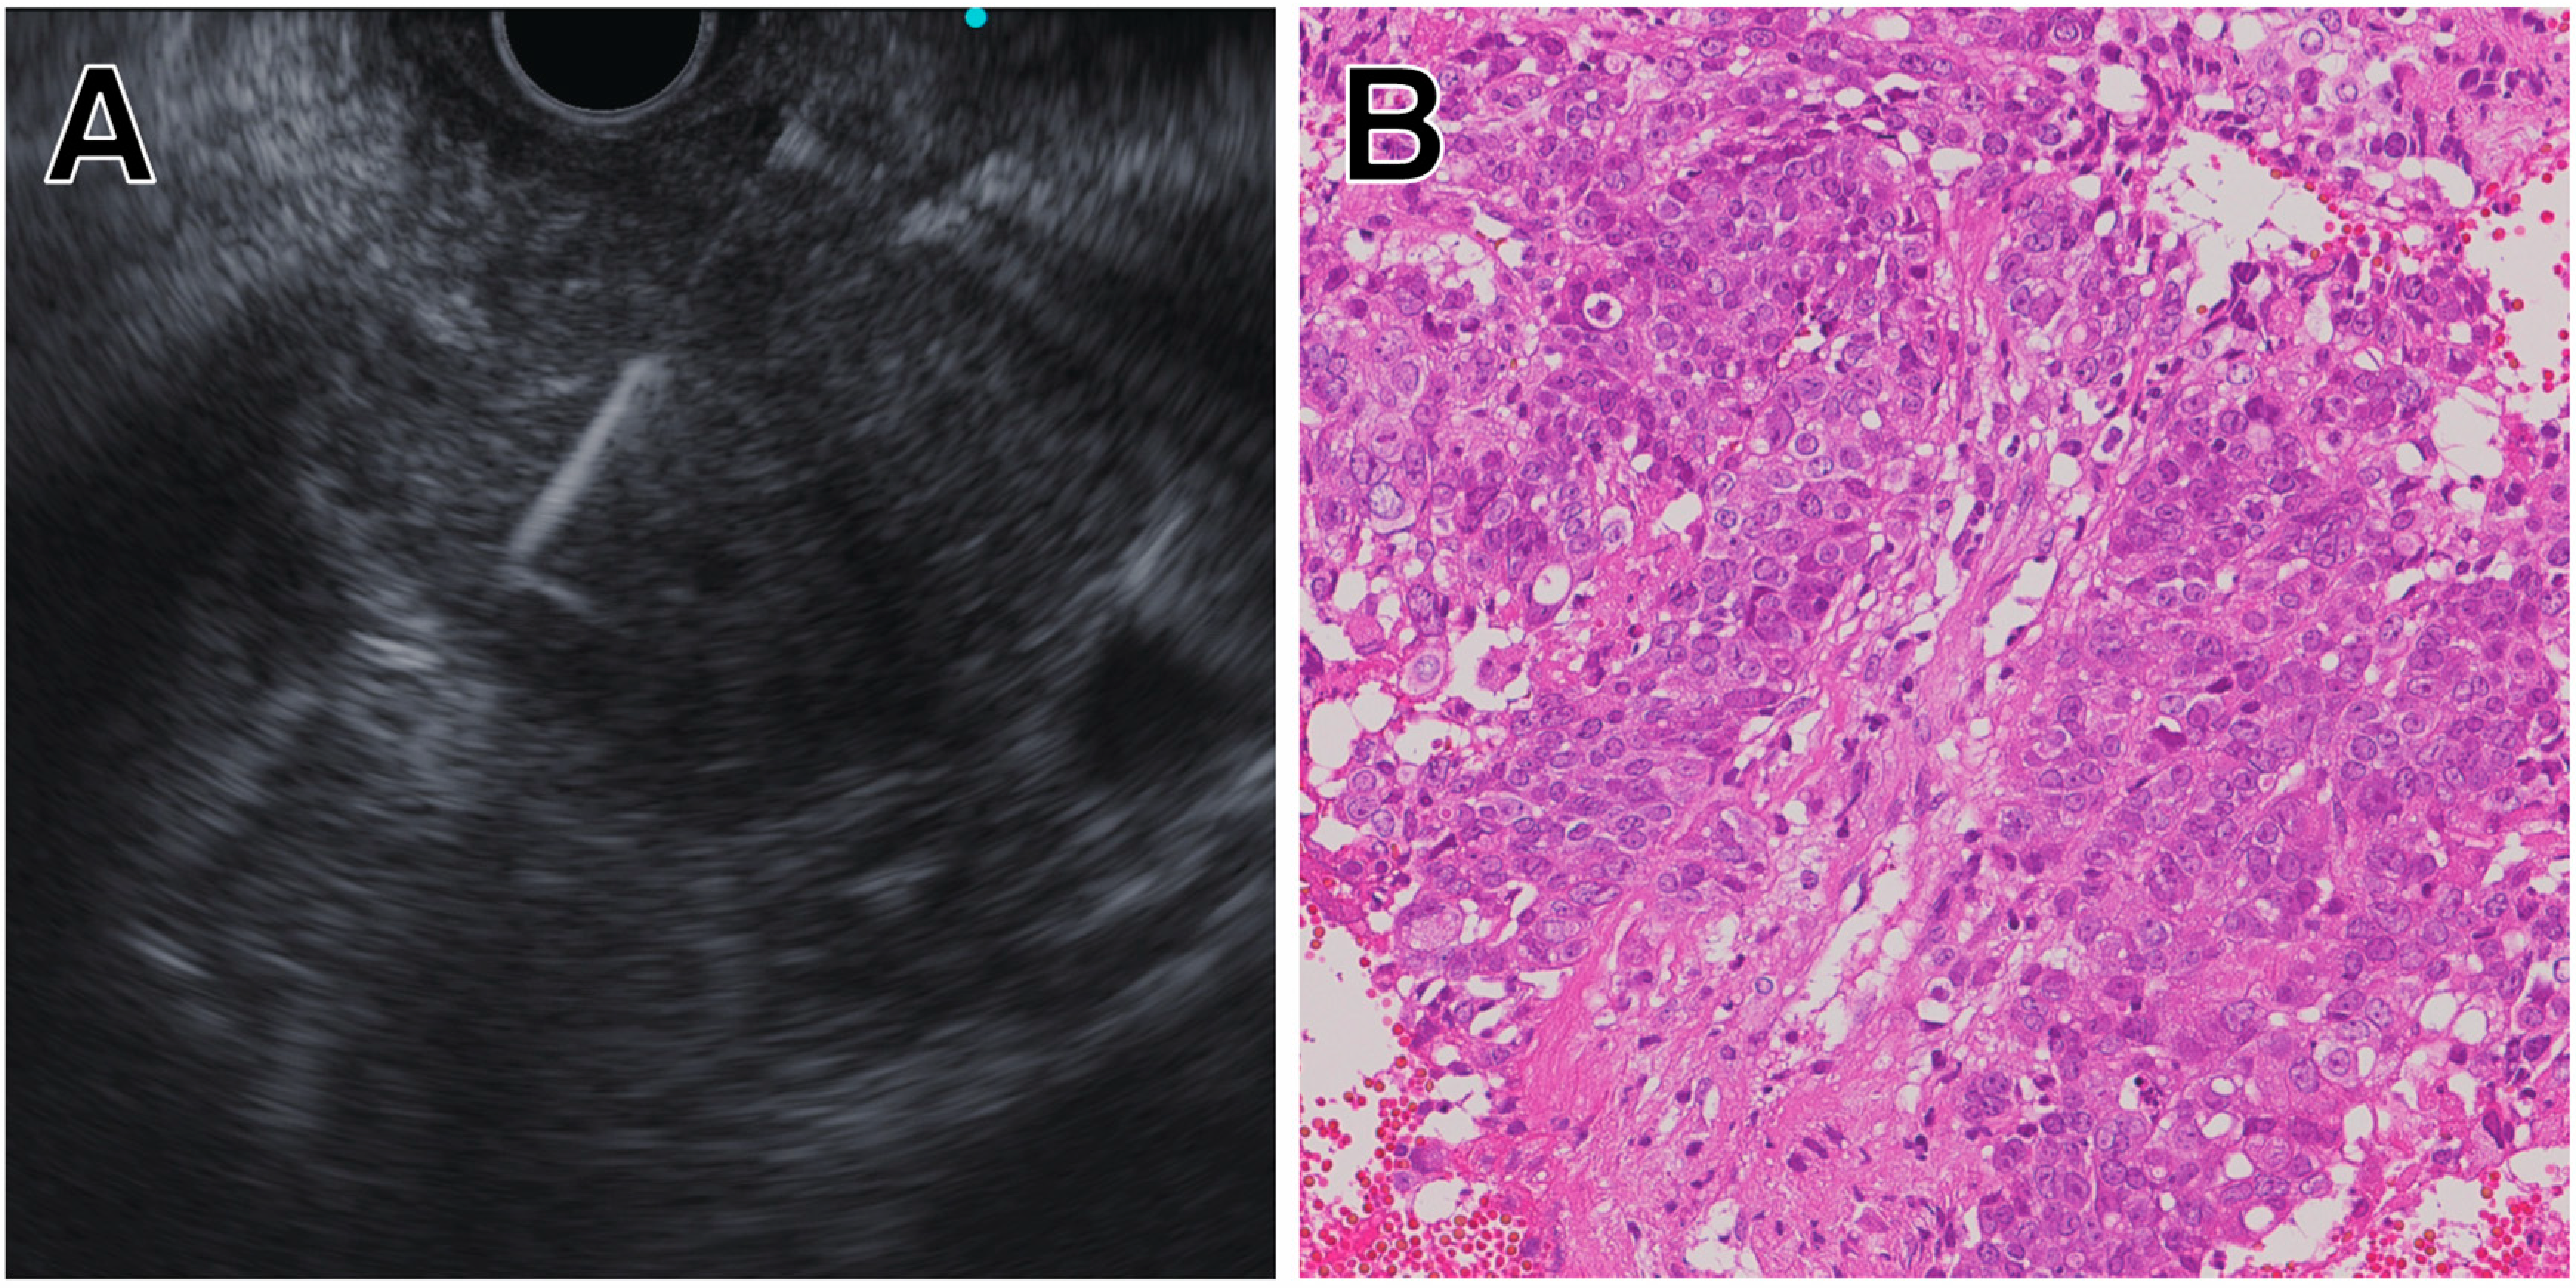

- Oh, D.; Seo, D.W.; Hong, S.M.; Jun, J.H.; Song, T.J.; Park, D.H.; Son, B.K.; Lee, S.S.; Lee, S.K.; Kim, M.H. The usefulness of contrast-enhanced harmonic EUS-guided fine-needle aspiration for evaluation of hepatic lesions (with video). Gastrointest. Endosc. 2018, 88, 495–501. [Google Scholar] [CrossRef]